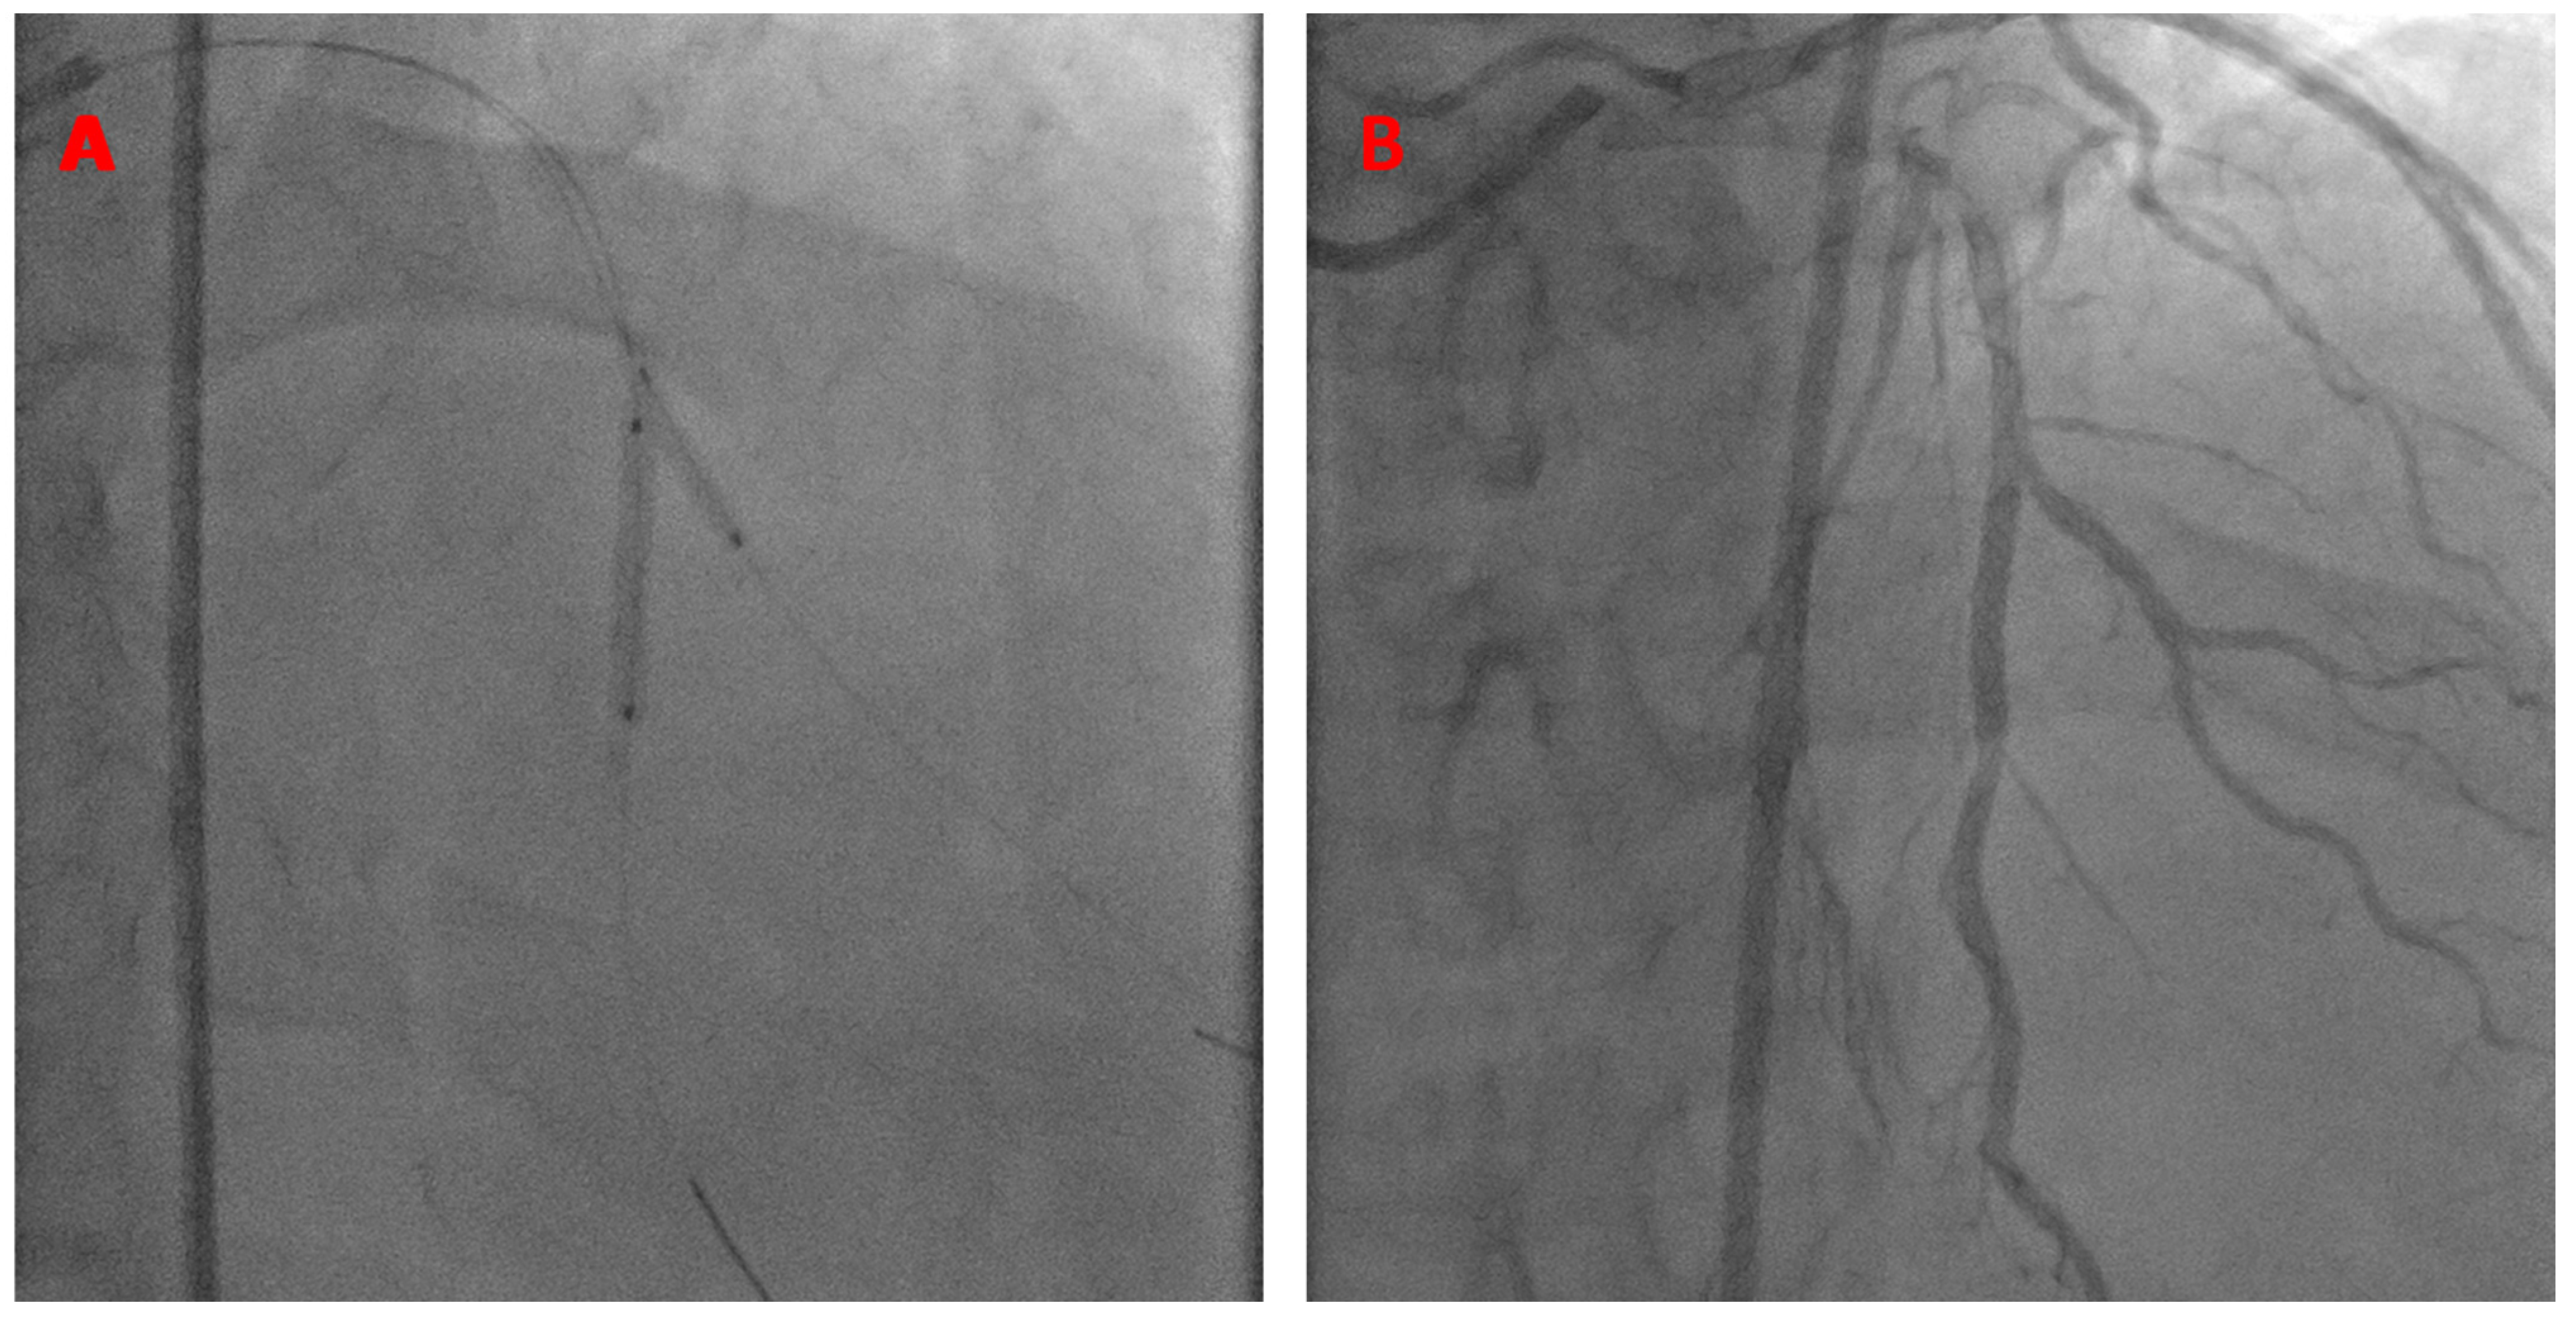

A 7 French JCL guide catheter was used to engage the left main coronary artery. The kissing BS technique was performed using a Xience Alpine 2.5 × 23 mm stent in the LAD (18 atm) and a 2.5 × 15 mm balloon in the diagonal branch (14 atm), as shown below (Figure 7).

Figure 7.

K-BS intervention on a mid-LAD/diagonal bifurcation. The stent is in the mid-LAD and the balloon is in the diagonal branch (A). Final angiographic results (B).

This patient presented 2 years later with similar symptoms of chest pain. He was referred for coronary angiography, which showed the patent LAD stent and native diagonal artery to be without significant disease. The FFR of the LAD was negative. No intervention was made at this time. The patient was seen in follow-ups 4 years post-intervention and continued to progress well clinically, without needing any further interventions (Video S5).